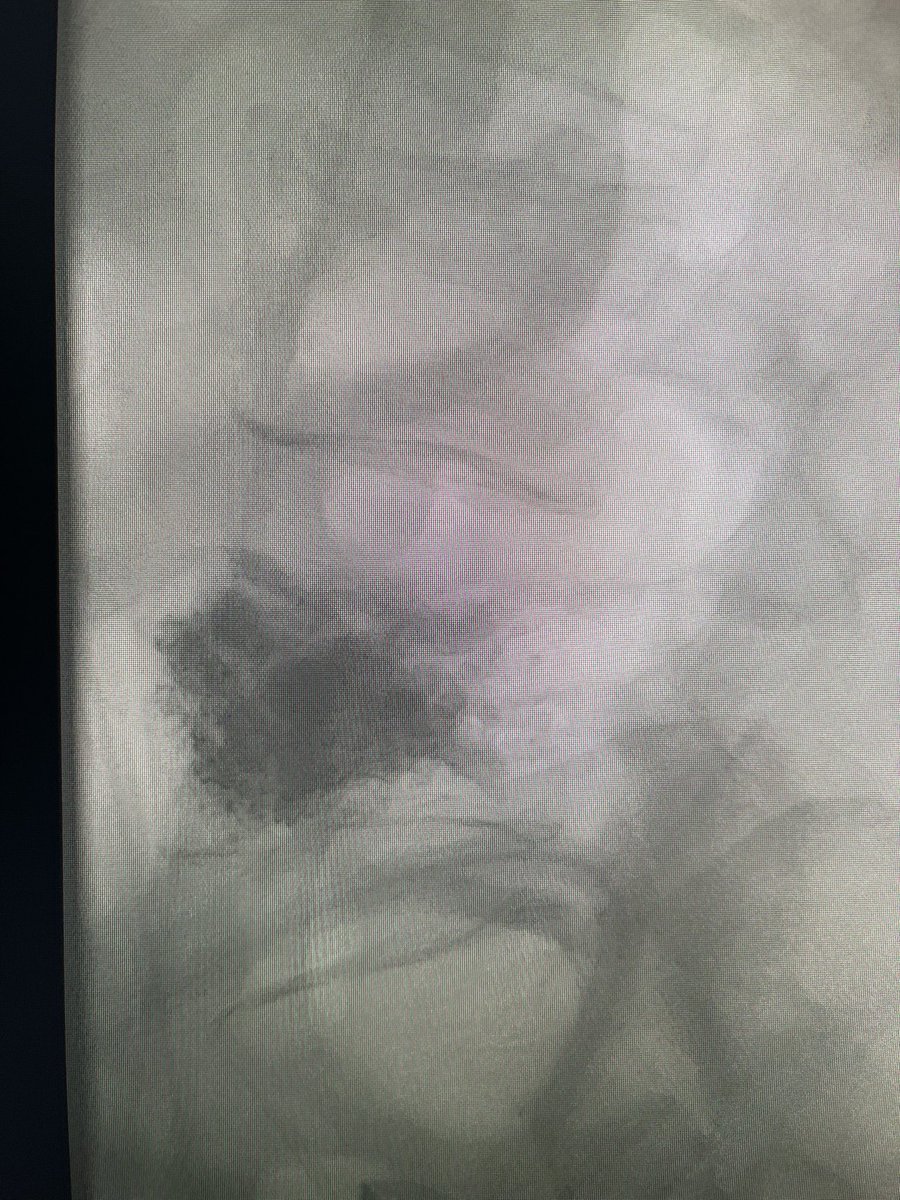

Excellent fill of the vertebral body with #KyphonVue! Only one way to truly celebrate such a good fill: #AirGuitar Thanks to @Coachkevin1026 for being the #BackupSinger

darthglader's tweet image. Excellent fill of the vertebral body with #KyphonVue! Only one way to truly celebrate such a good fill:

#AirGuitar

Thanks to @Coachkevin1026 for being the #BackupSinger